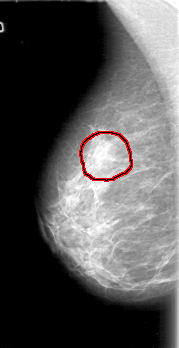

D_4066_1.RIGHT_CC

RIGHT_CC LINES 5116 PIXELS_PER_LINE 2641 BITS_PER_PIXEL 12 RESOLUTION 43.5 OVERLAY

FILE: D_4066_1.RIGHT_CC.OVERLAY

TOTAL_ABNORMALITIES 1

ABNORMALITY 1

LESION_TYPE MASS SHAPE ROUND MARGINS OBSCURED

ASSESSMENT 0

SUBTLETY 2

PATHOLOGY BENIGN

TOTAL_OUTLINES 1

BOUNDARY